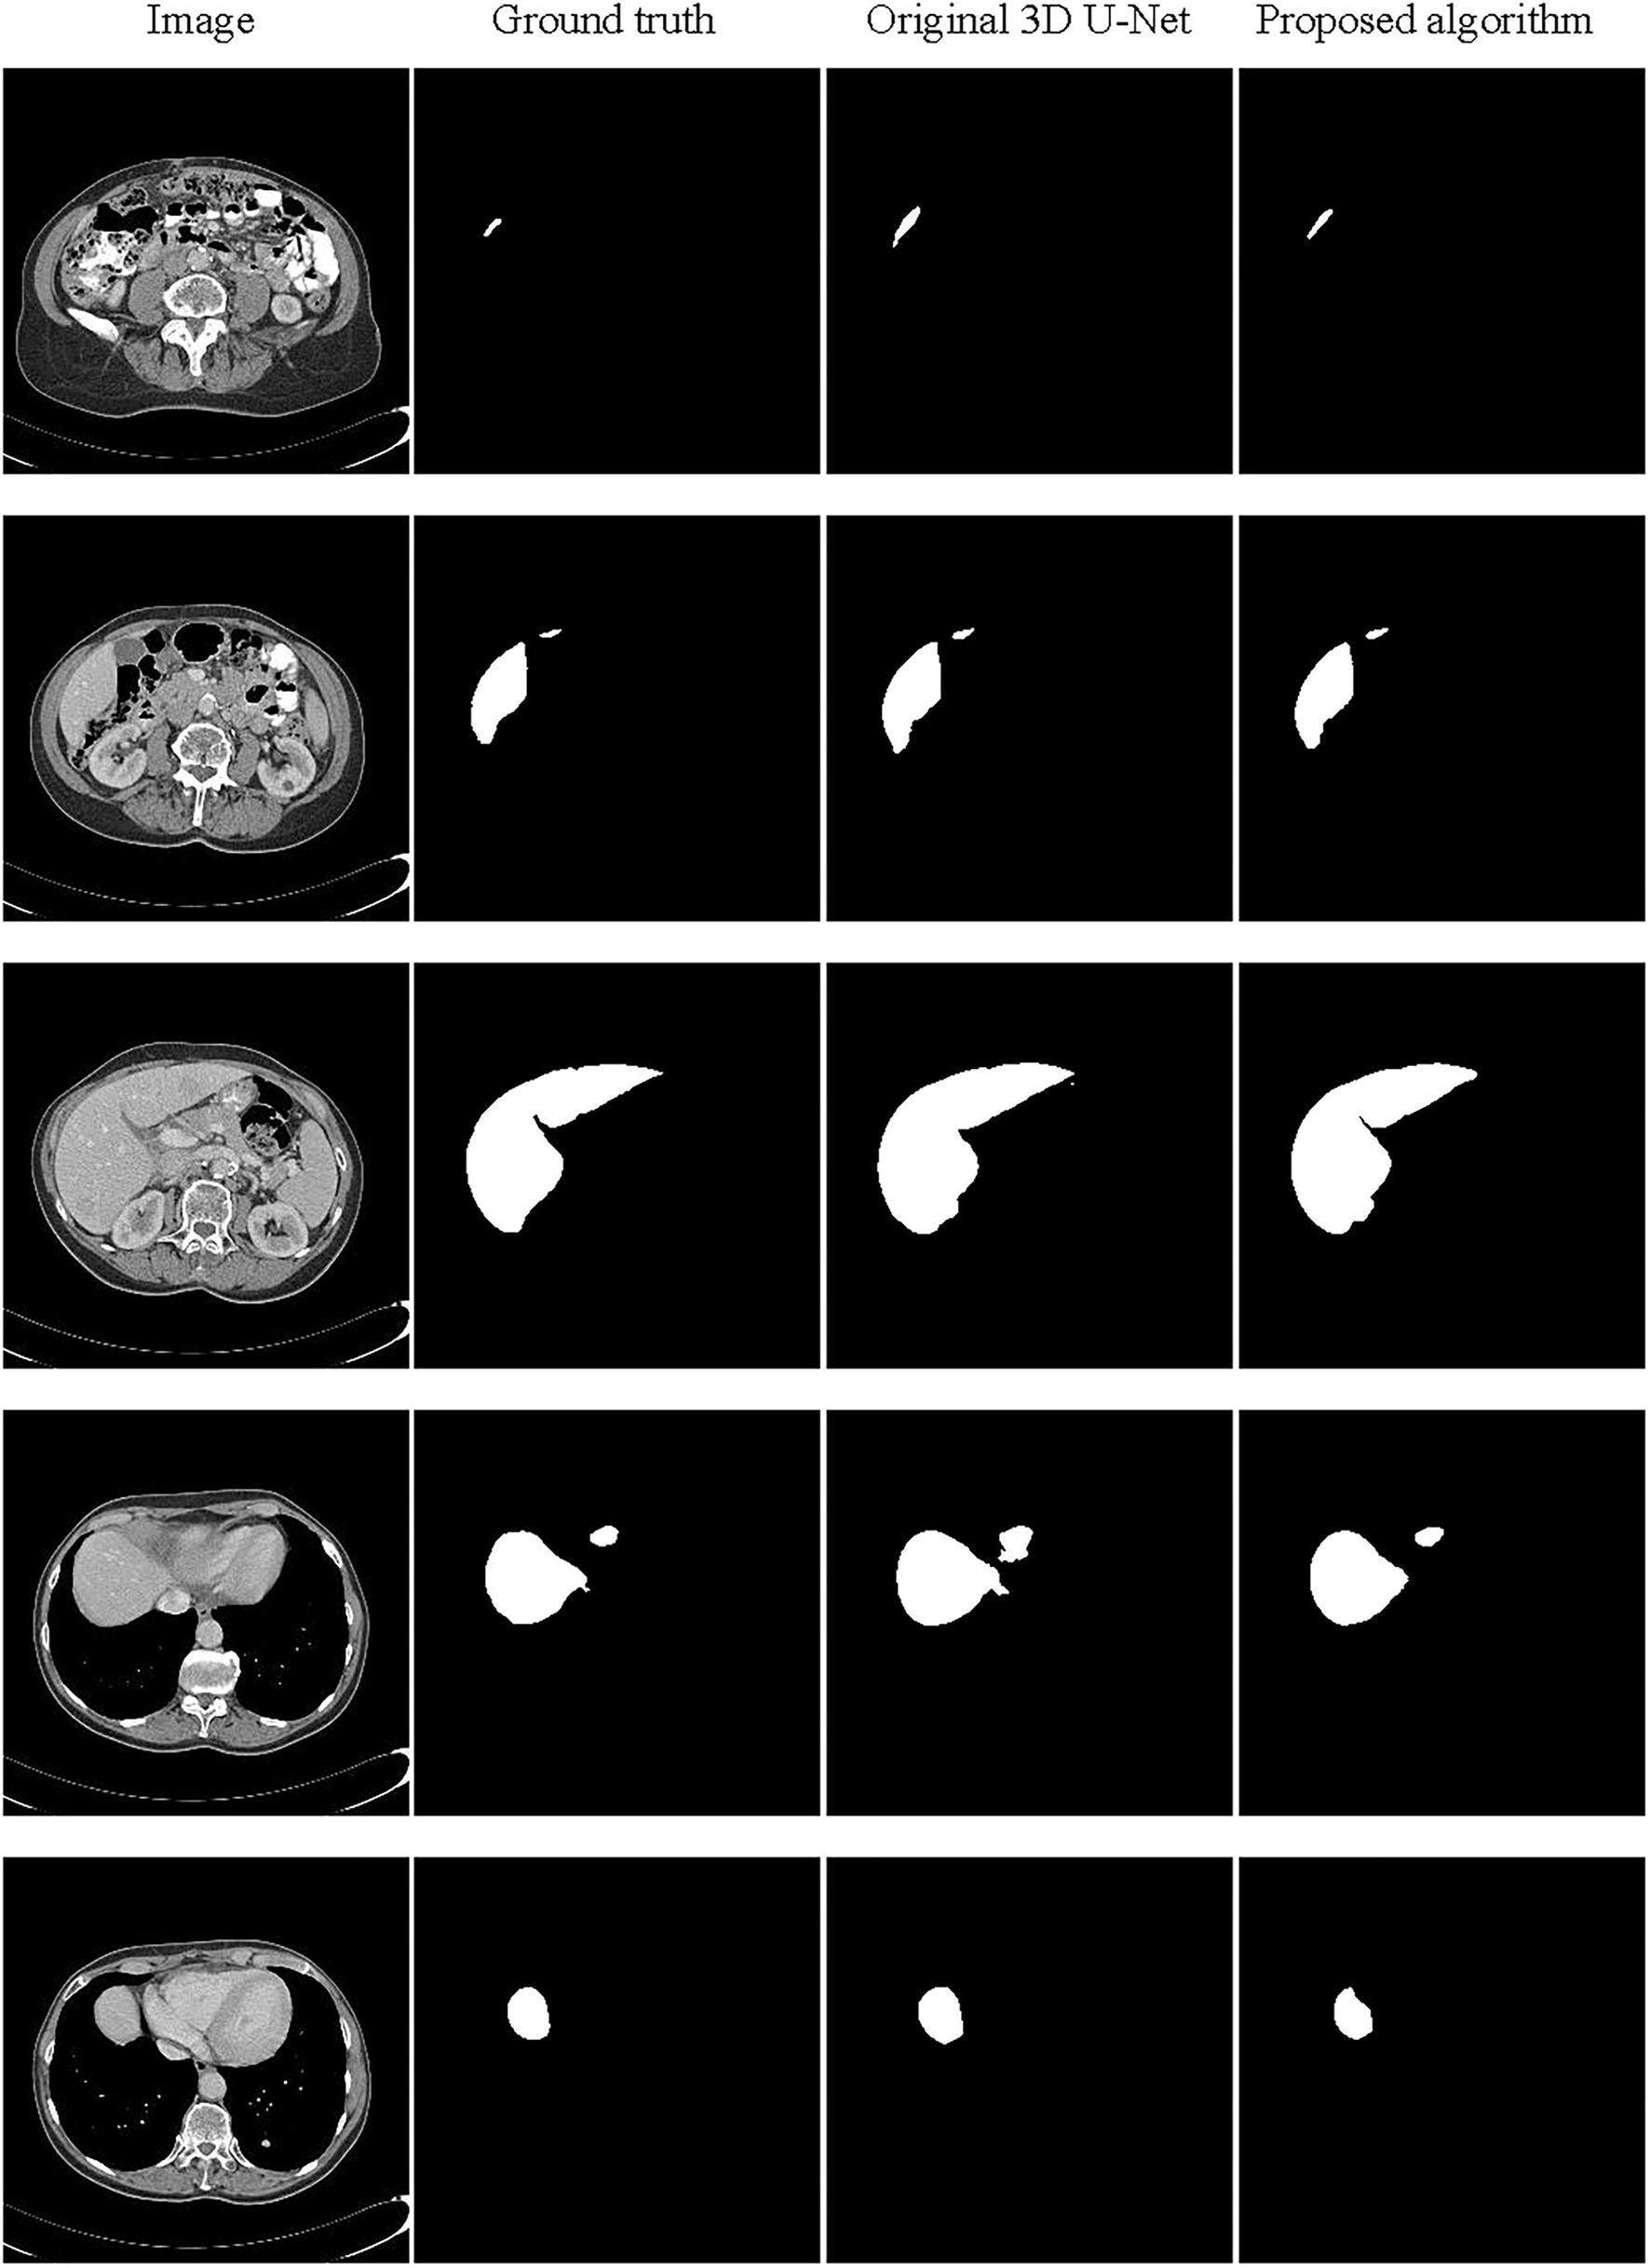

The Segmentation Results

The partial segmentation result is selected from the test set as shown in Figure 9. The first column is the original image, the second column is the ground truth, and the third and last column are the segmentation results by the original 3D U-Net and proposed algorithm. It can be found that using the proposed algorithm, the 3D segmentation results of the liver are very close to the real labels, which the problem of poor segmentation accuracy of head and tail regions of the liver has been improved. In order to further analyze the segmentation results, we have also supplied the 3D surface plots with the color bar of the Hausdorff Distance (HD).

Figure 9

Schematic representation of the liver 3D segmentation results.